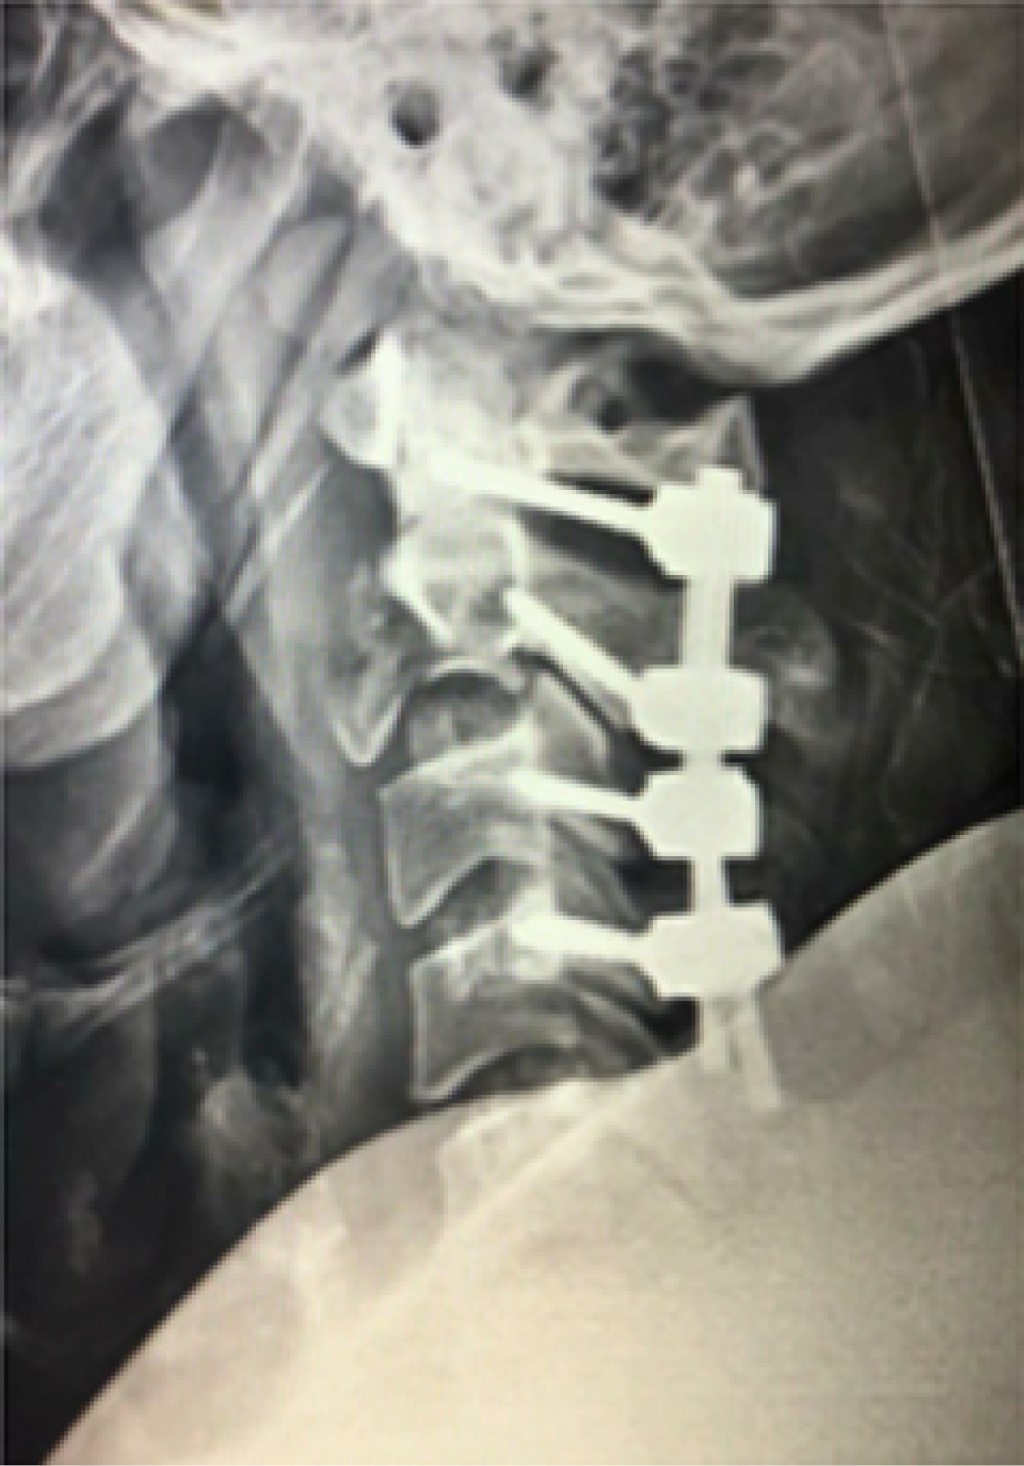

Cervical vertebral hemangioma with aggressive behavior

Introduction: Hemangiomas are the most common primary tumors of the spine. Mainly asymptomatic Incidental finding when performing an imaging study. The incidence reported at autopsies is 11% in the spine, multifocal lesions are present in 25 to 30% of cases. Clinical case: Vertebral cervical hemangioma with benign and stable characteristics that underwent surgical treatment, observing aggressive post-surgical behavior two months later. Conclusion: The approach to vertebral pathology is algorithmic and protocolized, it is necessary to determine the treatment based on the overall understanding of the disease and according to the clinical practice guidelines.

Figure 1

Figure 2

Figure 3

Figure 4

Figure 5

Figure 6